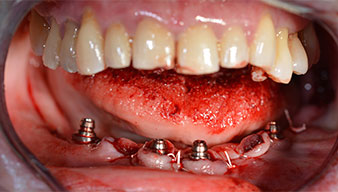

Направи се скенер с триизмерна компютърна томография (CBCT, Planmeca), за да се подпомогне планирането и да се намалят рисковете. Той показа, че качеството и количеството на наличната кост са достатъчни за операцията и имедиатното възстановяване, използвайки Fast & Fixed метод. Следвайки протокола за тази концепция, имплантите са поставени на 35, 32, 42 и 45 позиция. Ангулирането на дисталните импланти до 45° промени профила в задната зона и осигури по-голяма поддръжка в многоъгълната зона (Фиг. 3).

След отстраняване на частичното обеззъбяване в долната челюст, алвеоларният гребен е разкрит от 37 до 47.

Изходът на долночелюстния нерв е първоначално идентифициран като ограничена анатомична структура и, след това, кортикалната кост на гребена е загладена с прав наконечник и голям борер с розовиден профил (Фиг. 4).

Ангулираните абатмънти (35°) са завити в имплантите, за да компенсират отклонението от дисталните импланти, така че в резултат профилът на разположение на всички импланти да е възможно най-перпендикулярен на нивото на захапката. Това е предпоставка за оклузално поставяне на временна и впоследствие на постоянна протеза (Фиг. 15 и 16).

След това е взет отпечатък и е определена захапката на пациента, за да може зъботехникът незабавно да започне изработването на временната протеза. Протезата е поставена в същия ден (Фиг. 17 и 18).